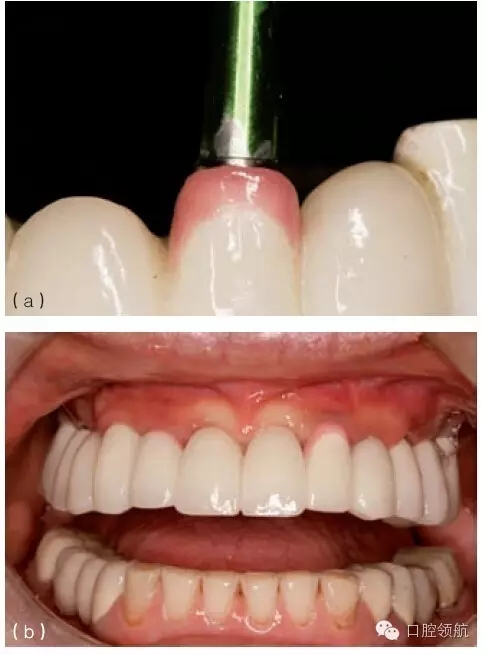

在種植體植入之前,有必要確定最終的修復(fù)方案,并且計算放置種植體修復(fù)部件所需要的空間。例如,對于單個粘結(jié)固位的種植修復(fù)體,從種植體平臺到對頜牙,最少需要7mm的空間。這個空間包括以下組成部分:基臺距對頜牙牙合面2mm;對粘結(jié)固位來說,即便聚合度非常平行的情況下,也至少需要4.5mm的預(yù)備高度,才能滿足固位要求;基臺與種植體交接的拋光肩領(lǐng)需要0.5mm。如果牙合間距離較?。ㄈ?.5~5mm),可以制作螺絲固位修復(fù)體(或UCLA的一體化冠)(圖9.23a,b)。實施種植手術(shù)時,必須考慮牙齦厚度及牙槽骨的水平。若有需要,可以施行牙槽嵴切除術(shù),以獲得額外的牙合間距離。另外,種植體可以高于、低于或平齊牙槽嵴頂,以便與未來的修復(fù)體匹配。但當(dāng)在修復(fù)期間考慮這些問題時,剩下的選擇就非常有限,只能在粘結(jié)固位或螺絲固位中選擇一種。有時,可以選磨對頜牙,來獲取少量的修復(fù)空間。另外,如果需要恢復(fù)垂直高度的話,可以通過升高咬合來獲得牙合間距離。

圖9.23 (a) 頰面觀, 牙合間距離不足(5mm)(相對于粘結(jié)固位),需要制作螺絲固位式修復(fù)體。(b)牙合 面和舌側(cè)觀,完成的螺絲固位式修復(fù)體。